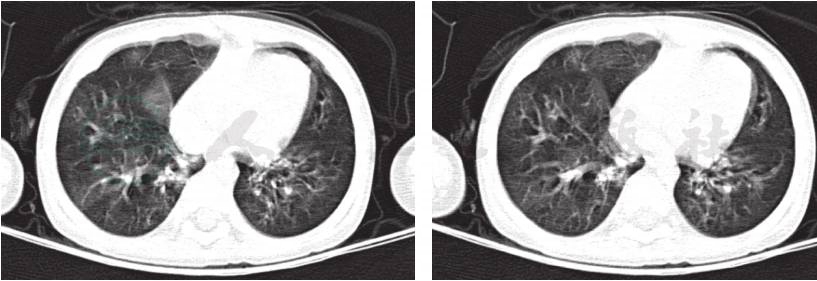

入院后完善各项检查:血常规、CRP等感染指标均正常;肺炎支原体抗体-IgM、IgG抗体均阴性;肺炎衣原体抗体阴性;结核抗体(TBAb)、常见呼吸道、肠道病毒及肝炎病毒检测均阴性,血细菌培养未见细菌生长,结核菌素试验阴性,G试验、GM试验阴性;免疫球蛋白及T淋巴细胞亚群无特殊异常。入院后予抗感染、布地奈德联合复方异丙托溴铵泵吸平喘治疗,但患儿喘息缓解不明显,结合病例特点及肺CT呈马赛克征改变,考虑为闭塞性细支气管炎,加用甲泼尼龙片[2mg/(kg·d),间隔 12 小时 1 次]、小剂量红霉素[5mg/(kg·d),每天2次]、乙酰半胱氨酸(600mg/次,每天1次)口服。期间患儿仍出现2次喘息加重及呼吸困难,均将口服甲泼尼龙片更换为静脉滴注甲泼尼龙琥珀酸钠[2mg/(kg·d)]、氨茶碱,患儿喘息略缓解。再次复查肺 CT(图3)示双肺多叶、段炎症部分吸收,右肺仍见部分实变改变较前未见明显变化,建议家属进一步完善支气管镜,行支气管肺泡灌洗术,以帮助明确病原,指导治疗,但家属拒绝。因患儿体温逐渐平稳,咳喘缓解,住院26天出院。出院医嘱:①口服甲泼尼龙片12mg,每天2次;②小剂量红霉素30mg/次,每天2次[5mg/(kg·d)];③乙酰半胱氨酸600mg/次,每天1次;④钙尔奇D 300mg/次,每天2次口服;⑤泵吸布地奈德0.25mg+生理盐水1ml/次,每天2次;⑥2周后门诊复查。

图3 入院后复查肺CT